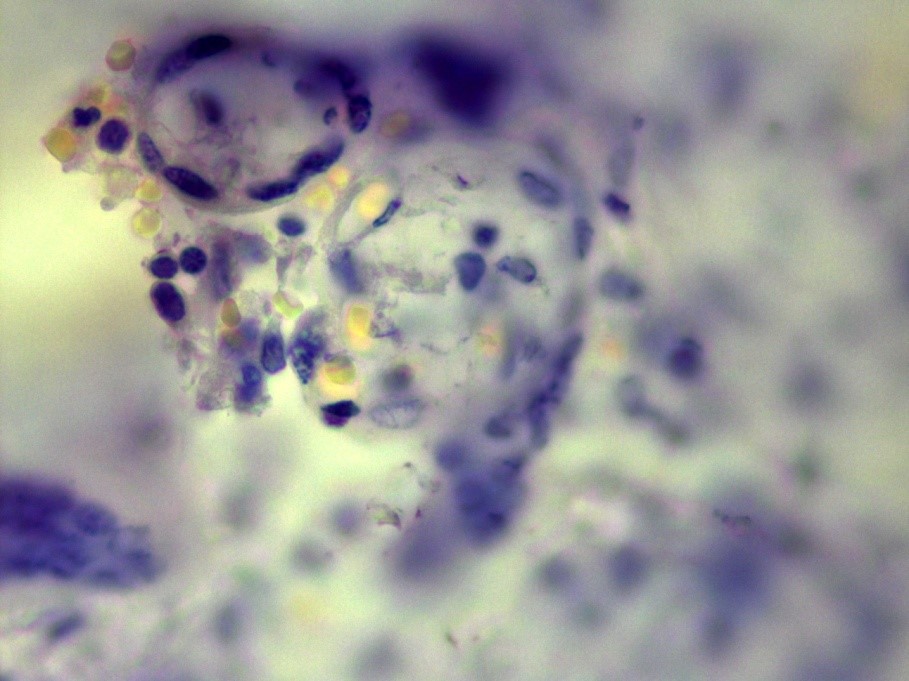

Our own case demonstrates an extremely rare case of TB of placenta in young woman, suffering from genital TB, which was overlooked before delivery. This woman had not known contact with TB infection, had no history of TB, had no complaints before pregnancy and had no special complaints in time of the pregnancy, excluding common ones for this condition. The delivery was in-time with a healthy full-term baby. In the Russian Federation the investigation of the placenta is a standard procedure, and it revealed TB inflammation (Figure 1) and Mtb in the placenta (Figure 2).